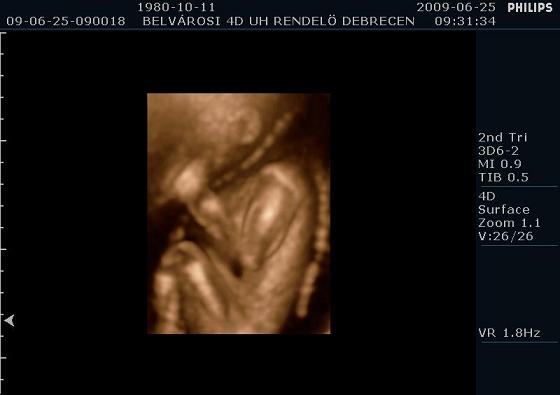

Mintha mosolyogna

Mintha mosolyogna

Profilból

Profilból

Férfiúi büszkeség

Férfiúi büszkeség  Bokszolni készül

Bokszolni készül

A kis izmos fiam

A kis izmos fiam